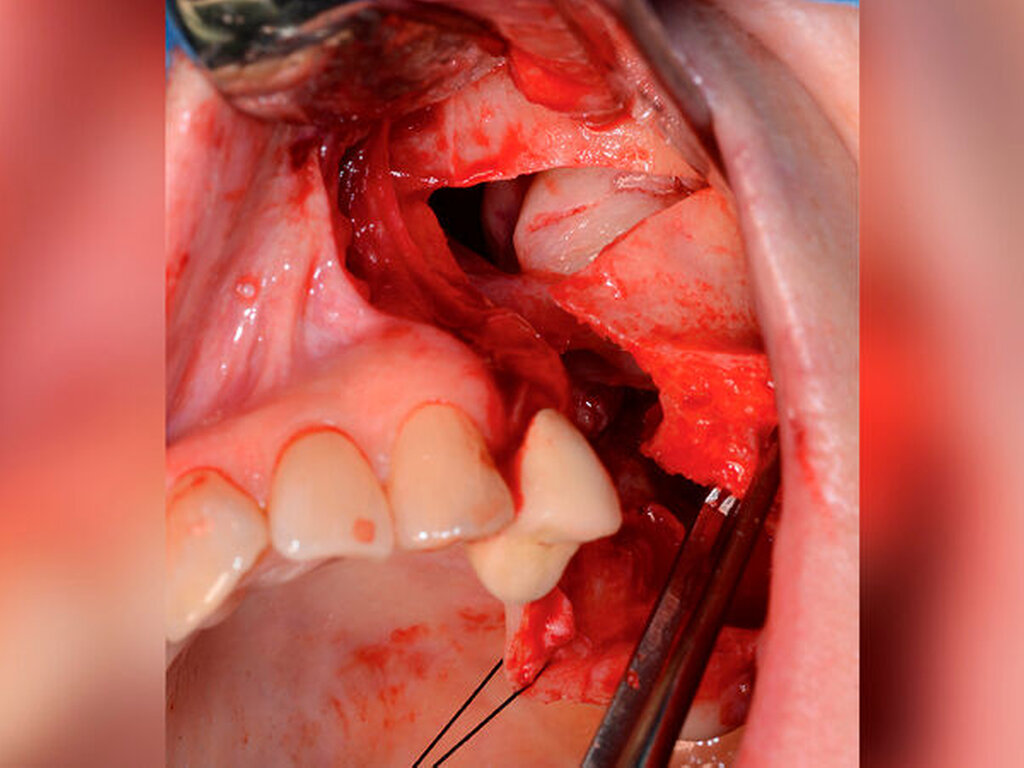

Es wurde die Indikation zur Entfernung der Raumforderung samt Extraktion des Zahnes 25 gestellt. Nach crestal palatinaler Inzision und Umschneidung der MAV konnte ein mukoperiostaler Lappen gebildet und die faziale Kieferhöhlenwand großflächig dargestellt werden. Der Zahn konnte komplikationslos entfernt werden. Zur Einhaltung eines ausreichenden Sicherheitsabstands erfolgte die großflächige Osteotomie des linken Oberkiefers mit der Knochensäge bis zur anterioren Kieferhöhlenwand parallel zur Okklusionsebene (Abbildung 2). Distal erfolgte das Absetzen mit dem Obwegeser-Meißel. Der Befund konnte anschließend in toto entfernt werden (Abbildung 3) und die MAV mittels einer plastischen Deckung nach Rehrmann unter Verwendung des Bichat‘schen-Fettpfropfs mehrschichtig verschlossen werden.

In der Histopathologie zeigte sich der Befund eines 3,8 cm großen muralen (Infiltration in die Zystenwand) Ameloblastoms mit plexiformem und zystischem Wachstumsmuster – von einer Resektion in toto mit einem Sicherheitsabstand von > 1,5 mm konnte ausgegangen werden. Eine Transformation in ein malignes Ameloblastom war nicht nachweisbar. Im Rahmen der nun dreijährigen Nachsorge konnte kein Hinweis auf ein Rezidiv gesehen werden. Eine Rekonstruktion des Knochens wurde bisher von der Patientin bei nicht vorhandenen Einschränkungen der Mastikation und der Phonation abgelehnt.